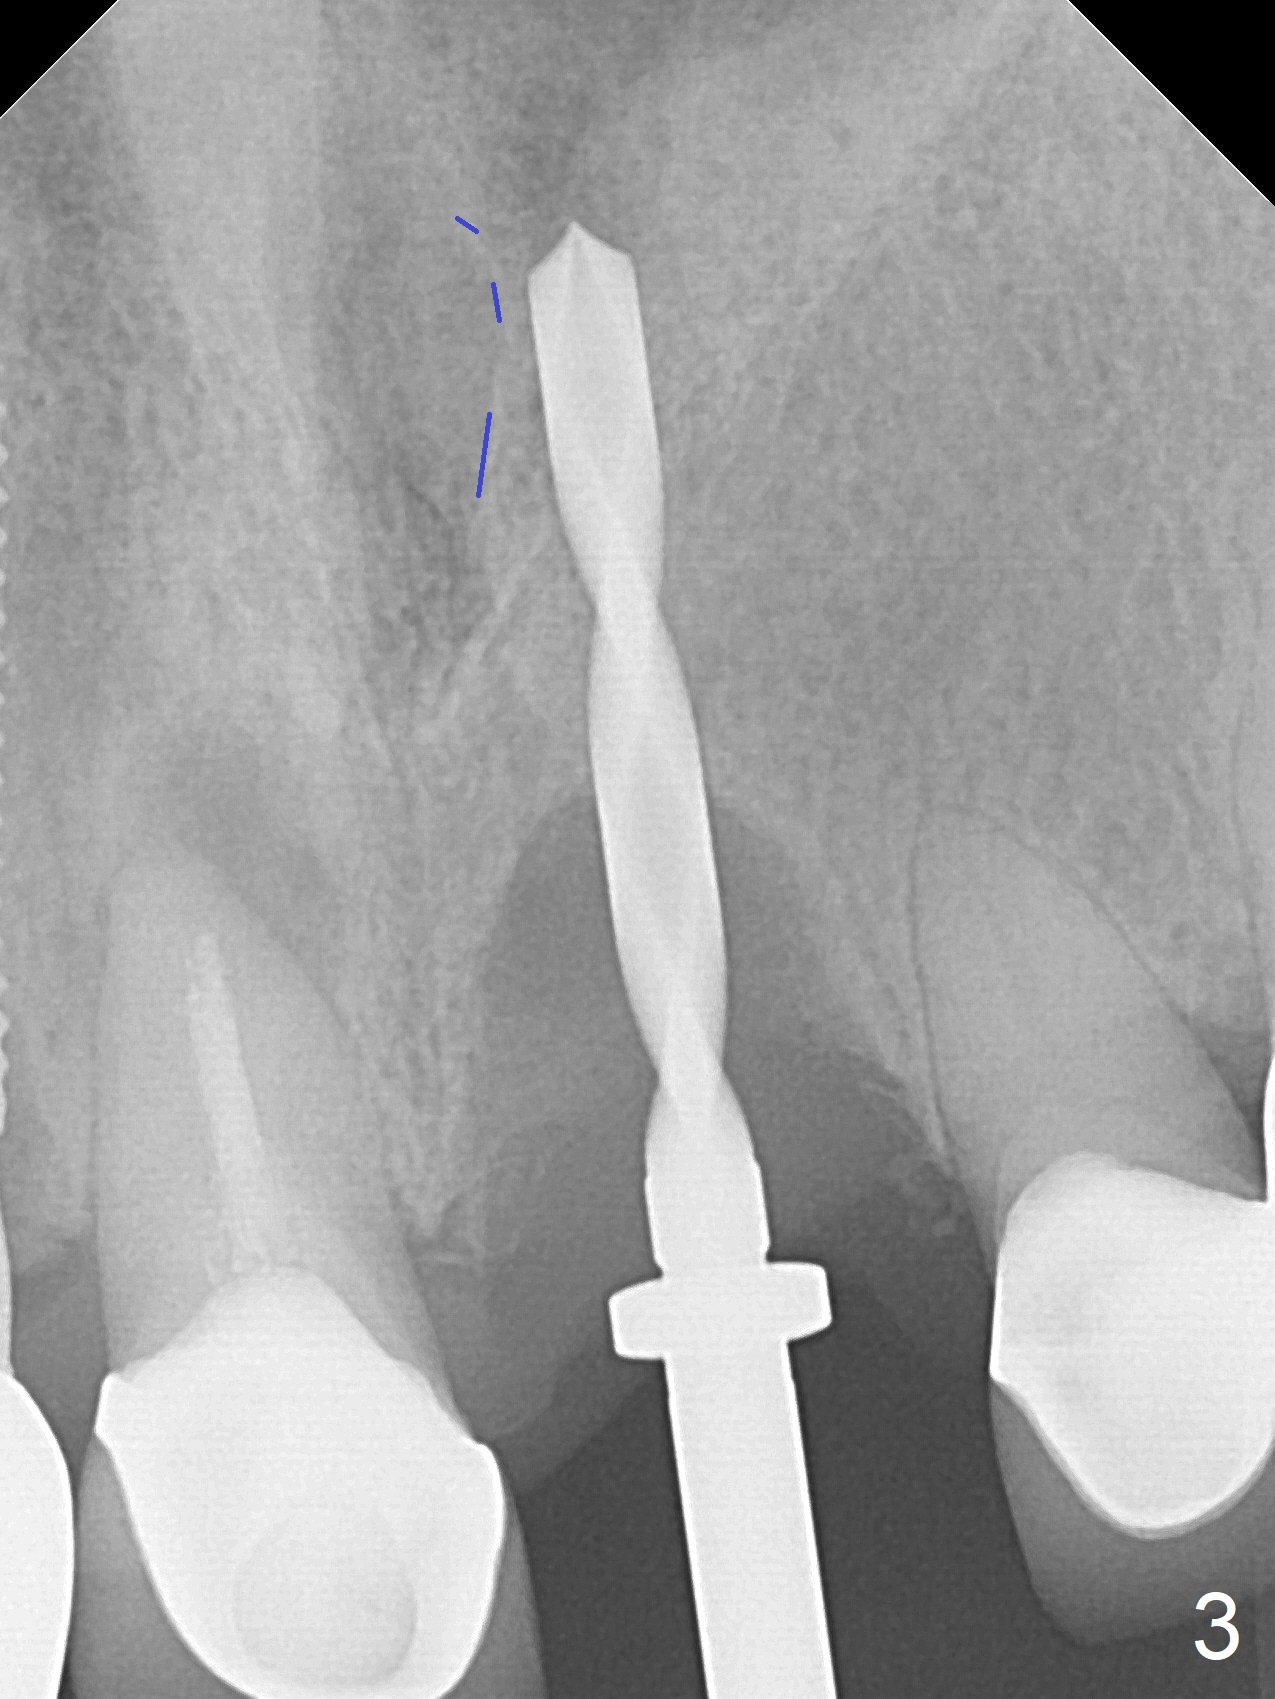

3.8x15 mm Implant with Proximity to

Nasal Floor

The buccal contour at #9 seems to be slightly concave preop (Fig.1,2 (*)). In fact the buccal plate is found to be lost when the tooth is extracted. Osteotomy is initiated as palatal as possible apical, but the occlusion dictates the coronal end of the osteotomy should be buccal, leaving the buccal gap ~ 2 mm for bone graft. The initial osteotomy (18 mm deep) appears to be close to the Incisive Foramen (Fig.3 blue dashed line). The nasal floor appears to be intact when the drill is removed. Subsequent osteotomy is adjusted so that the apical end of the osteotomy moves distal; when a 3.8x15 mm dummy implant is partially placed, there is clearance (Fig.4). It remains so when a definitive implant is seated (Fig.5); Vanilla graft is placed (Fig.5 *) before placement of a 4.5x5.5(3) mm abutment. More allograft is placed when an immediate provisional is fabricated (Fig.6 arrow and *). The gingiva remains to be recessive 1 month postop (Fig.7). It seems to be related to the bulky gingival margin of the provisional (Fig.8 *). After trimming the latter (Fig.9 *), the gingival margin immediately returns close to normal (Fig.10). The gingival margin is even between #8 and 9 two months postop, but the bone graft is exposed apically (Fig.11 ^). It may heals by itself. Otherwise debridement, regraft, PRF and suture are pending. The coronal portion of the socket heals 4 months postop (Fig.12). The gingival cuff forms by the immediate provisional (which is removed for impression) 4 months postop (Fig.13 *). While the full Zirconia crown at #7 remains intact (Fig.14), the PFM at #9 has porcelain chip (Fig.15). It is partially due to the occlusion; while the crown at #7 has clearance with the opposing dentition (Fig.16 *), the one at #9 has no. The access hole at #9 (Fig.17 *) seems to weaken the crown structure. There is no access hole at #7. No solid posterior support is another contributing factor for chip (Fig.18). The buccal plate has mild atrophy at #7 and 9 (Fig.19 *). A piece of bone graft is being expelled apically at #9 (Fig.20 >) and is removed subsequently (Fig.21). Before impression for repacking porcelain, the opposing incisal edge has been shortened (Fig.22 arrows, as compared to Fig.16). Since the ideal access hole is at the incisal edge (Fig.25 black circle), buccal to the existing one (Fig.24 A), the abutment is torqued before the repaired crown is recemented (Fig.23). Finally the crown has occlusal clearance (Fig.26). Porcelain chips again around the access hole of PFM 1.5 years post 2nd cementation. The dense bone at the crest (*) cannot explain why the abutment is not loose, since it remains incompletely seated (>). As it was trimmed short, an angled abutment is used (Fig.28). The coronal end is lingual, while #9/24 is edge to edge. The lingual aspect of the coronal end of the abutment is heavily trimmed to reduce bulkiness. To prevent chip, Zirconium crown will be fabricated in spite of the fact that it does not match the PFM of #8 (potential shade discrepancy). The patient is pleased with the new Zirconia crown (Fig.29).